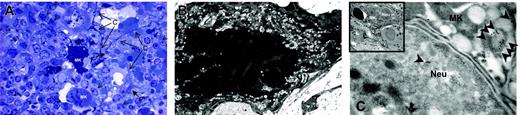

The Mks in the spleen from TPO-treated wild-type mice expressed several morphologic abnormalities characteristic of GATA-1low Mks. Semithin (A) and ultrathin (B-C) sections of the spleen from TPO-treated wild-type mice. The semithin section (A) shows a cluster of light- and heavy-electron dense Mks (Mk) surrounded by numerous neutrophils (arrowheads), fibroblasts (F plus arrows), and connectival fibers (CF). Upon ultrastructural examination (B), heavy-electron dense Mks present a morphology of cytoplasm and nucleus compatible with that of cells undergoing para-apoptosis.22 Furthermore, heavy-electron dense Mks contain neutrophils (Neu) embedded in their cytoplasm (insert in C), as proved by immunogold staining for myeloperoxidase (C) that shows gold particles (arrowheads) in the cytoplasm both of the neutrophil and of the Mks. Similar results were observed in the spleen of at least 3 separate TPO-treated wild-type mice. Magnification: × 100 (A), × 3000 (B, insert in C), and × 30 000 (C). Numerical aperture of the objective lenses: 0.1.

TPO treatment had profound effects on the morphology of Mks both in wild-type and GATA-1low mice. In wild-type mice, the overall morphology of the Mks in the spleen became less mature, as revealed by reduced localization of P-selectin (Schmitt et al32 and results not shown) and von Willebrand factor (Table 2) on the α-granules. In addition, a significant portion (31 ± 2.6%) of these Mks had the heavy-electron dense para-apoptotic morphology originally described for GATA-1low Mks22 and contained neutrophils embedded in the cytoplasm, as confirmed by myeloperoxidase immunostaining (Figure 4). In contrast, in TPO-treated GATA-1low mice, the morphology of the Mks became more mature with clearly delineated platelet territories and significant increase, both in number and in localization to the α-granules, of von Willebrand factor–related gold particles (Figure 5; Table 2). These stage III Mks, never detected in untreated mutants,22 represented 28.5% of the Mks in spleen from TPO-treated GATA-1low Mks.